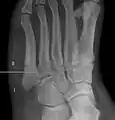

Diagnostic X-rays include anteroposterior, oblique, and lateral views and should be made with the foot in full flexion.

Proximal fractures of the fifth metatarsal bone:

- Proximal diaphysis, typically stress fracture.[12][13]

- Metaphysis: Jones fracture[14]

-Tuberosity: Pseudo-Jones fracture[15] (avulsion fracture).[15]

Pseudo-Jones fracture